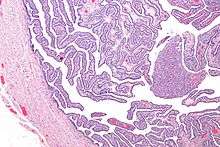

Definitive criteria include histopathologic evidence of endometritis, thickened filled Fallopian tubes, or laparoscopic findings. Gram stain/smear becomes definitive in the identification of rare, atypical or and possibly more serious organisms.[20] Two thirds of patients with laparoscopic evidence of previous PID were not aware they had PID, however even asymptomatic PID can cause serious harm.